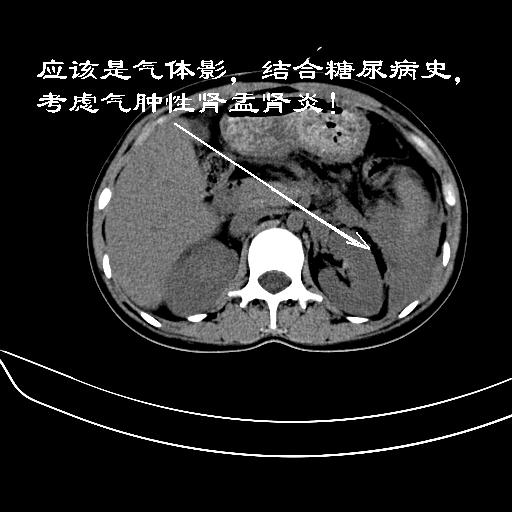

女,22岁,临床以糖尿病等病史入院,两年前有妊娠合并胰腺炎史,现有多饮、多尿、咳嗽、咳痰、左腰痛、发热等。因多种原因没做增强。

肝、脾增大,内见多发低密度影,少量腹水,左侧肾周筋膜增厚,结合病人糖尿病史,有左腰痛、发热,考虑:糖尿病激发肝脾病变(梗塞?),左侧肾周感染,建议进一步检查。

真可惜,这么年轻就重病缠身,患者肝内,脾,肾,左下肺,左腰大肌均见病变,结合病史考虑感染可能性大。

考虑感染性病变,糖尿病最常见的并发症就是感染